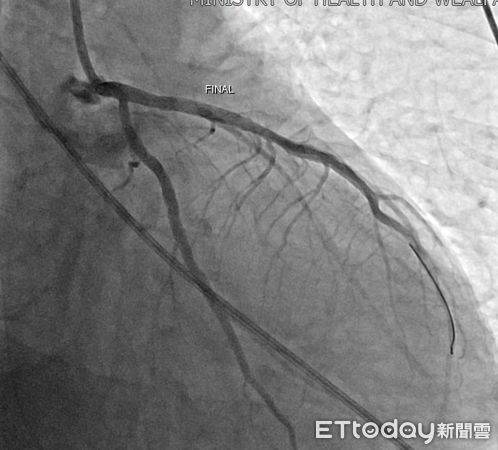

▲心臟裝置支架術後。(圖/嘉義醫院提供)

急診醫護團隊第一時間施行高品質心肺復甦術(CPR)、電擊除顫及氣管插管等緊急處置,成功讓患者恢復自主心跳,並迅速轉入心導管室,由心臟內科羅勖中醫師緊急接手治療。經心導管檢查發現,患者左前降支(LAD)幾乎完全阻塞,為典型導致猝死的致命型心肌梗塞。羅醫師果斷進行冠狀動脈介入治療,於極短時間內開通阻塞血管並植入支架,有效恢復心肌灌流,爭取到救命的黃金時間。